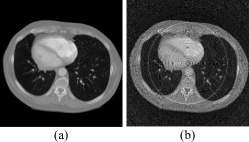

Figure 9: Real data and FBP[26] results. (a) Unprocessed sinogram and its CT image. (b) Sinogram with black gaps removed using linear interpolation and its CT image. The display range is [0, 3.144] for the sinograms and [0, 0.010] for the CT images.

The real data experiment was conducted using a 120 kV X-ray source (Libra13UlNE, iRay, China) to generate X-rays. The detector used was a Flat-Panel Photon Counting Detector (EIGER2, DECTRIS, Switzerland). The scanned sample was a fresh pork trotter. Fig. 8 shows the PCD-CT system and the scanned sample. The scanning configuration was consistent with that of the simulated data experiments. Fig. 9 shows the sinogram data collected during the experiment. The first row of Fig. 9 (a) shows the reference sinogram, where black stripes caused by the gaps between the FPCD panels can be observed. Most existing stripe artifact removal methods struggle to handle artifacts caused by defective pixels, such as these black gaps. To comprehensively evaluate the performance of the proposed method, linear interpolation was used to preprocess these black gaps to evaluate the performance of the proposed method comprehensively. The first row of Fig. 9 (b) shows the preprocessed sinogram. To ensure fairness in the comparison experiments, the relevant parameters of the compared methods were fine-tuned from their default settings to achieve optimal stripe artifact removal performance.

Figures 10 (a), (b), (c), and (h) show the results of stripe artifact removal from the sinogram containing black gaps in Fig. 9 (a). All methods successfully removed the black stripes and reduced other stripe artifacts. The results of the combination method [14] in Fig. 10 (a) demonstrate its effectiveness in removing stripe artifacts. The overall image is clear, and details are well-preserved. However, in the local zoomed-in regions, some ring artifacts remain. Fig. 10 (b) shows the result after applying flat-field correction and linear interpolation for defective pixels (black gaps), followed by TV-L1subscript𝐿1L_{1} aG filtering. The results indicate that while details are well preserved, noticeable ring artifacts remain in the local zoomed-in regions. Fig. 10 (c) uses a dual-domain regularization iterative method. The reconstructed results still show slight ring artifacts in the local zoomed-in regions. Fig. 10 (h) presents the results of the proposed method, where defective pixels (those at the black gaps) were not involved in the neural network training. These defective pixel values were predicted by the network 𝐅𝚯subscript𝐅𝚯\mathbf{F}_{\mathbf{\Theta}}. The proposed method can maintain image continuity while filling gaps and effectively controlling ring artifacts. Figures 10 (d) to (g) show the experiments on stripe artifact removal from the sinogram after linear interpolation of the black gaps in Fig. 9 (b). Although these methods improved the quality of the reconstructed images and reduced ring artifacts to some extent, residual ring artifacts can still be observed in the local zoomed-in regions. The proposed method in Fig. 10 (f) best preserves image continuity and reduces ring artifacts.

In summary, when comparing the methods in Fig. 10, the method in Fig. 10 (a) is relatively complex, achieving good stripe artifact removal results but still leaving slight ring artifacts. The methods in Fig. 10 (b) and Fig. 10 (c) require extensive parameter tuning to achieve satisfactory results. Methods in Fig. 10 (d) to Fig. 10 (g) leave some residual ring artifacts. Fig. 10 (h) provides the best ring artifact removal and the clearest reconstructed image. Comparative analysis shows that the proposed method effectively removes ring artifacts, whereas other methods leave varying degrees of ring traces in the reconstructed images.